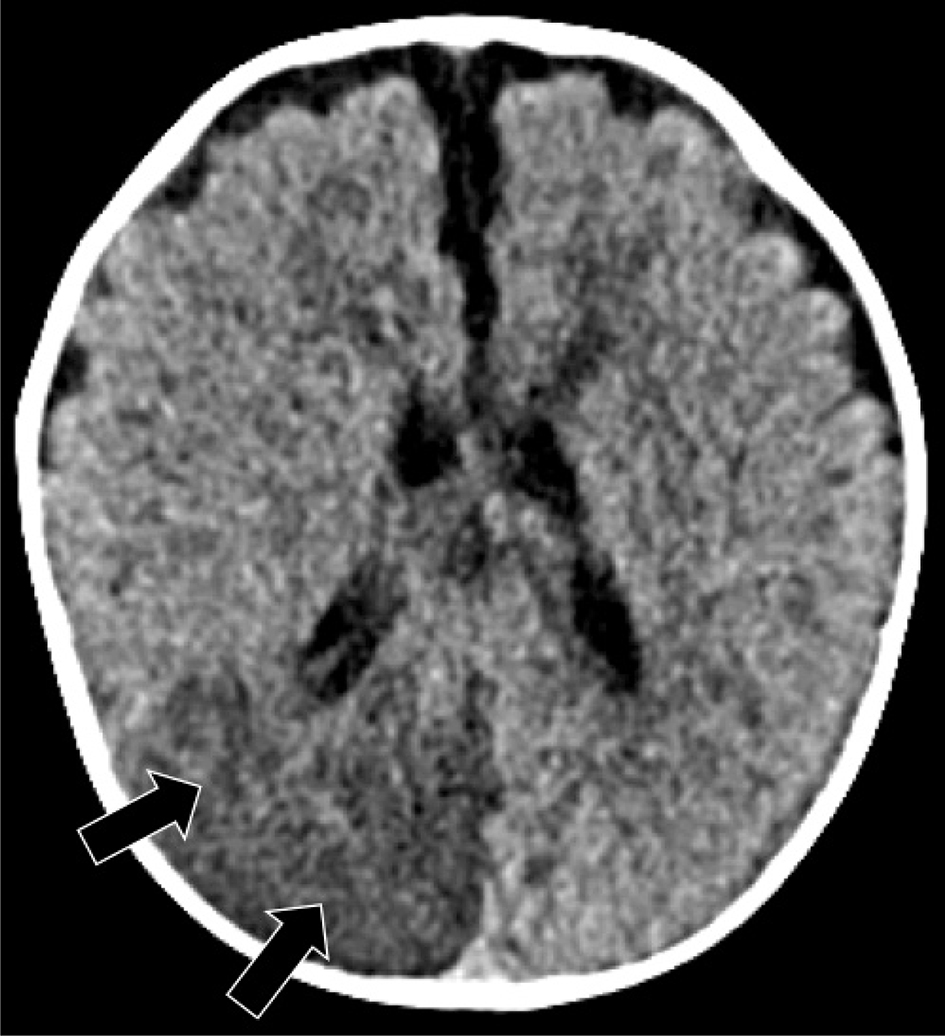

Venous infarct/CSVT

Pediatric venous infarcts secondary to CSVT/thrombosis of medullary veins occur most often (more than 40%) in the neonatal period (88, 89). The reported incidence of venous thrombosis is 2.6 per 100,000 (1, 88, 90). Approximately 50–60% percent suffer venous infarction, of which about 75% are hemorrhagic (21). The suggested pathophysiology of venous thrombosis encompasses “Virchow’s triad”, including: stasis of blood flow, injury to the endothelial lining, and hypercoagulability of blood components (94). As in perinatal AIS, multiple risk factors in both the mother and fetus may play a role in neonatal venous thrombosis, including gestational diabetes, preeclampsia, chorioamnionitis, neonatal sepsis, dehydration, difficult or instrumented delivery, and underlying prothrombotic state (95, 96). Venous thrombosis should be suspected in the setting of an unexplained hemorrhage or a brain parenchymal injury that does not fit an arterial vascular distribution, in the absence of trauma or infection (73, 97). Venous sinus occlusion initially reduces venous outflow with resultant vasogenic edema, and if adequate collateral venous outflow is not established, venous infarction will ensue (98). CT is sensitive for detecting hemorrhage, although the risk of ionizing radiation should be considered. On CT, venous infarcts are usually poorly delimited, hypodense, or mixed-attenuation, likely related to the presence of cerebral edema and hemorrhage, without respecting arterial territories (Figure 9) (42). The thrombosed vein may be seen overlying the infarction as a curvilinear region of high attenuation, depending upon the age of the thrombus. Infarctions occur in the territory of thrombosed venous, with parasagittal injuries in superior sagittal sinus thrombosis, temporal lobe hematomas in transverse sinus thrombosis, and thalamic hemorrhage in vein of Galen and straight sinus thromboses (99).

Fig 9

Figure 9. Venous thrombosis and hemorrhagic venous infarction. A three-day-old girl with right sided seizures. Axial non-contrast CT images show left frontal hemorrhagic venous infarction (arrow) and hyperdense clot in the superior sagittal sinus (arrowheads). Case courtesy of Dr. Tamara Feygin, Department of Radiology, Children’s Hospital of Philadelphia.